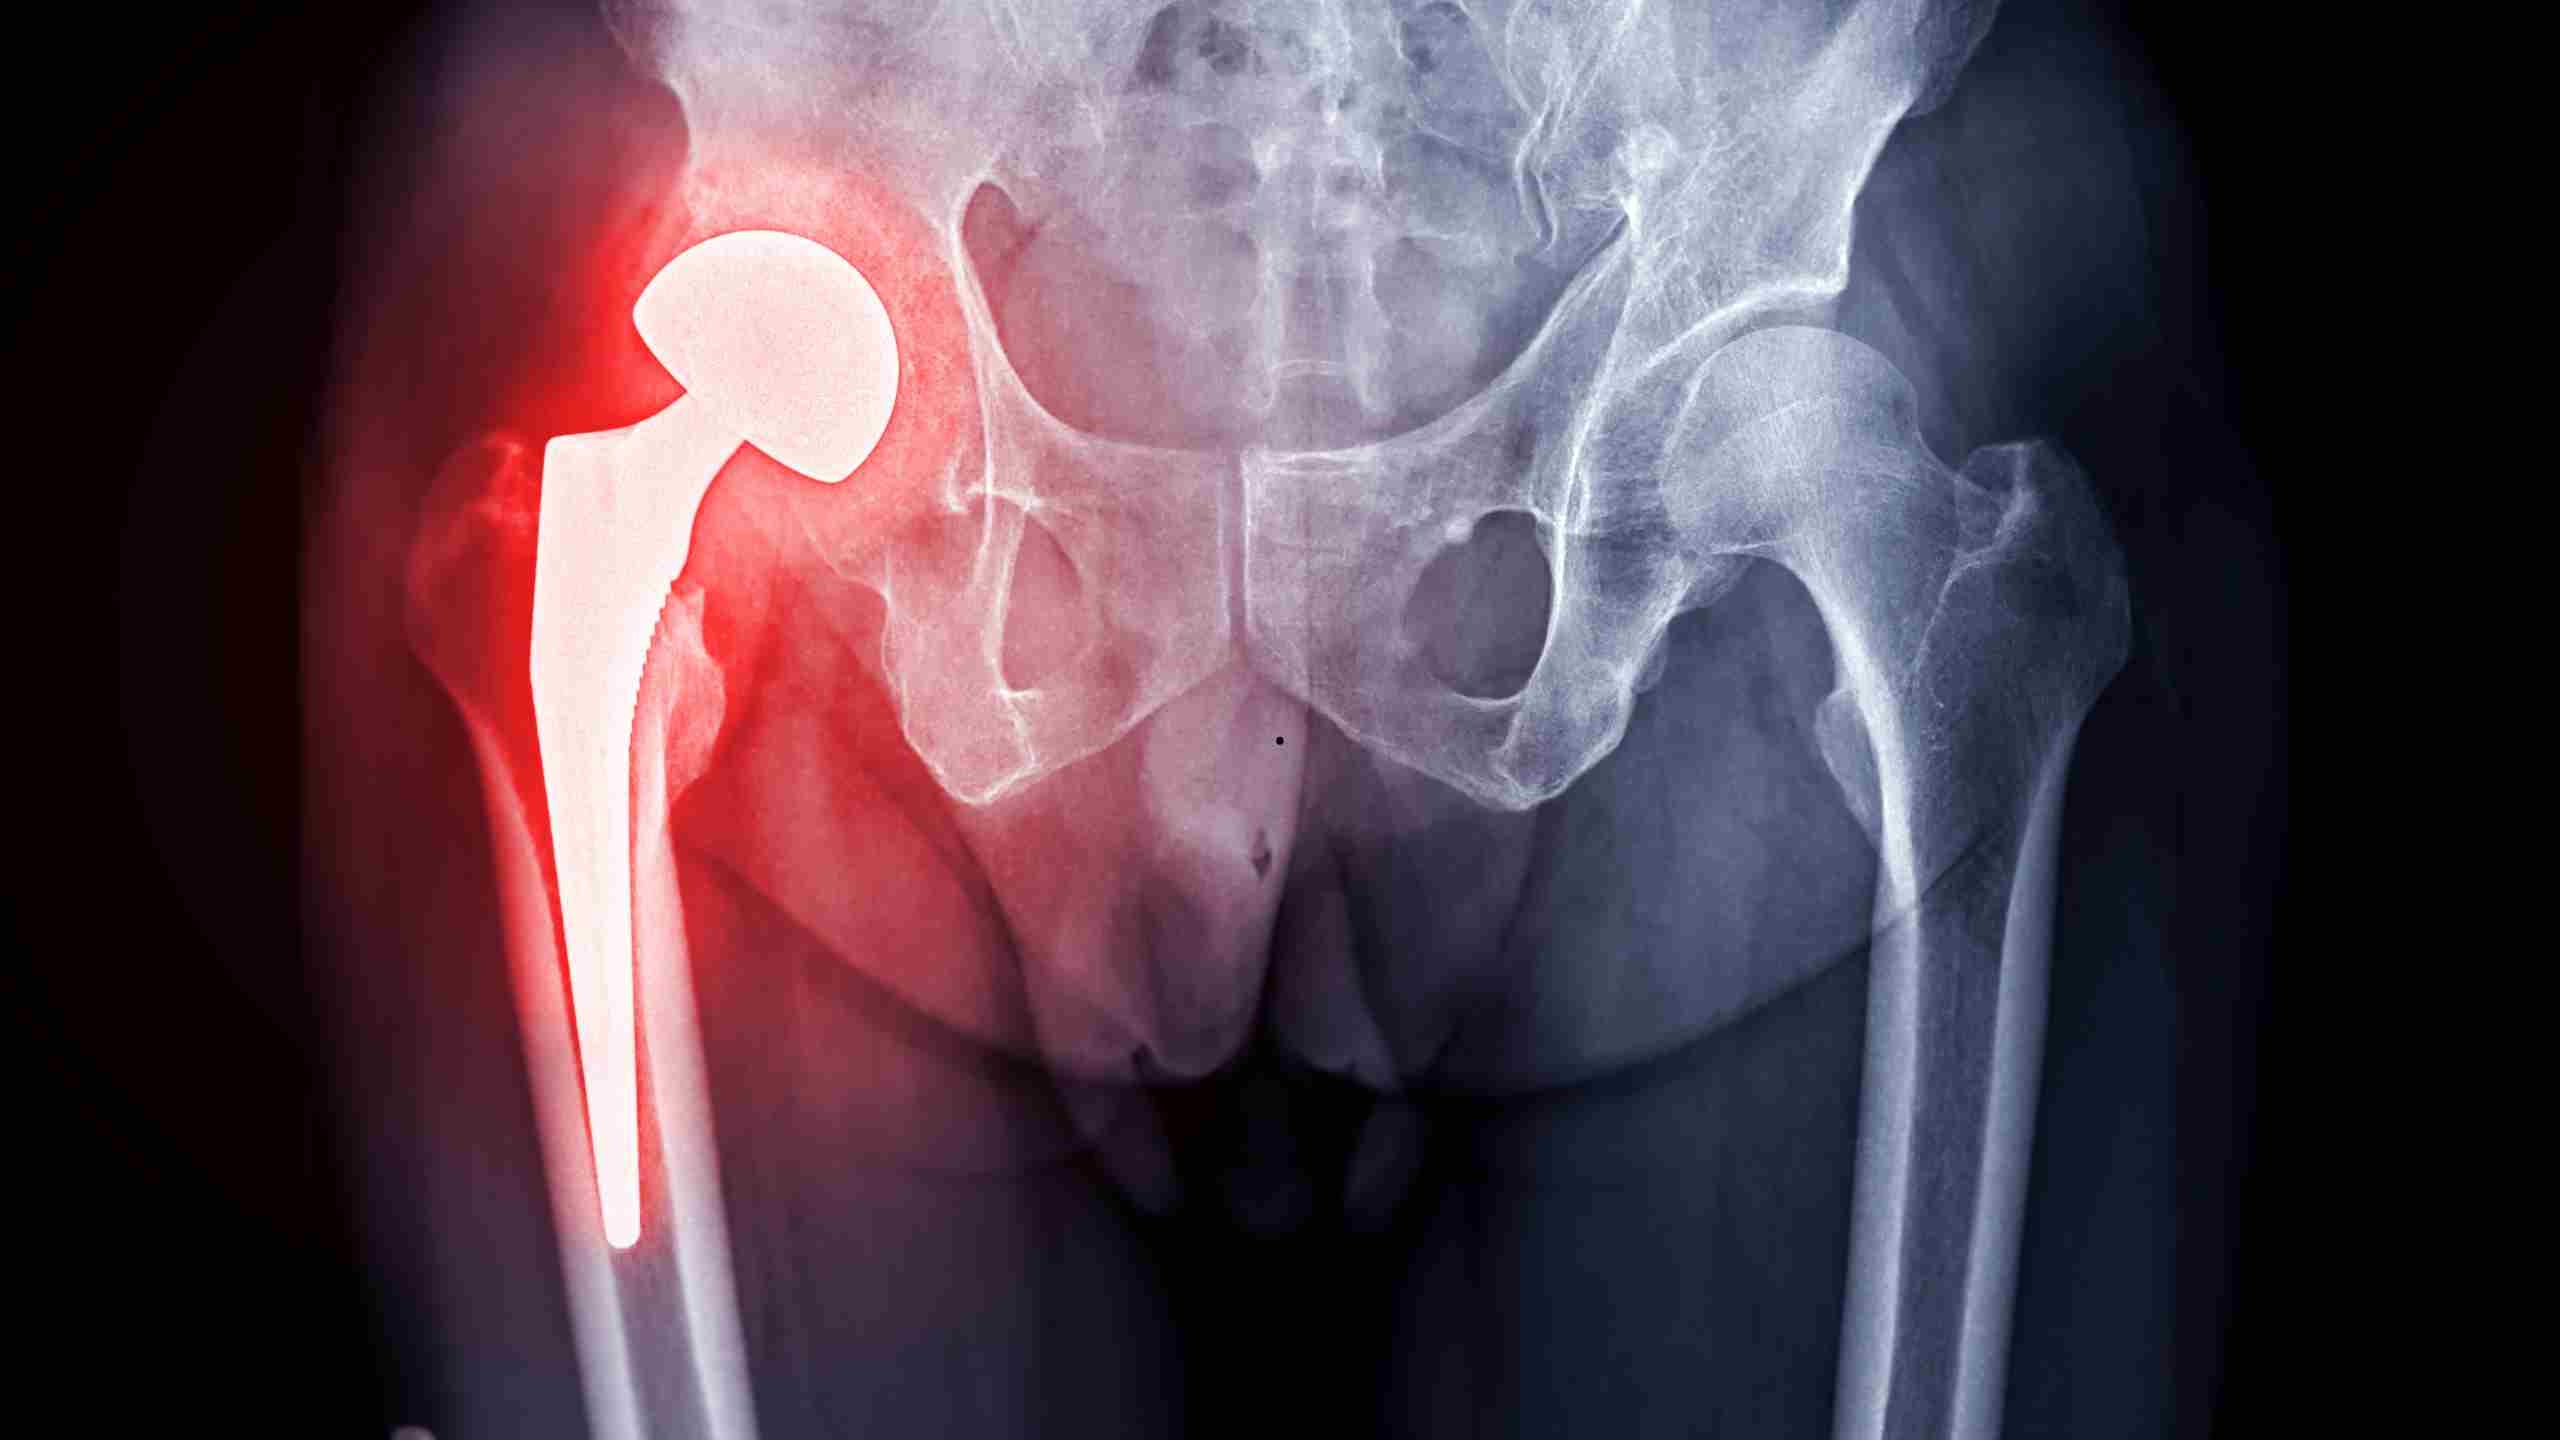

Descellement de prothèse de hanche: causes, symptômes et solutions

Imaginez une chaise bancale. Vous voyez le pied qui se décolle ? Eh bien, c’est un peu pareil avec une prothèse de hanche. Le descellement, c’est quand la fixation entre l’os et la prothèse lâche un peu. Ça peut être à cause de l’usure, d’une infection ou juste parce que, ben, le corps n’est pas toujours d’accord avec les trucs qu’on y met.

- Radiographie : Pour checker si la prothèse a bougé ou non.

La PTH (prothèse totale de hanche) classique remplace l’articulation usée. Elle comprend une cupule cotyloïdienne et une tête fémorale en métal ou céramique.